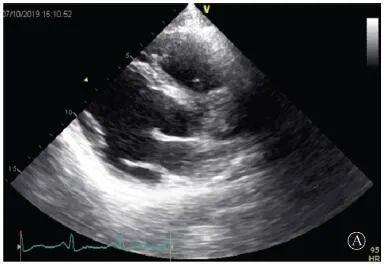

患者入院后無特殊不適,心率70次/min,血壓110/60 mmHg,心功能Ⅱ級。查血常規(guī):血紅蛋白139 g/L,白細胞7.39×109/L,血小板221×109/L。尿常規(guī)、便常規(guī)+潛血均正常。生化:丙氨酸氨基轉(zhuǎn)移酶38 U/L,白蛋白47 g/L,鉀3.9 mmol/L,肌酐(酶法)65 μmol/L,總膽固醇3.52 mmol/L,低密度脂蛋白膽固醇2.08 mmol/L。CK:1256→487 U/L,CK-MB 9.7→3.8 μg/L,cTnI 85.90→68.50 pg/ml。N末端B型利鈉肽原70 pg/ml。CK同工酶電泳:肌酸激酶MM質(zhì)量100.0%(此時CK-MB已正常)。血沉1 mm/第1小時,高敏C反應蛋白1.61 mg/L;補體:C3 0.876 g/L,C4 0.174 g/L。免疫球蛋白:IgG 9.52 g/L,IgA 1.73 g/L,IgM 0.62 g/L。血清蛋白電泳未見M蛋白。糖化血紅蛋白5.1%。乳酸(運動前)1.1 mmol/L,乳酸(運動中)6.6 mmol/L,乳酸(運動后)7.8 mmol/L。肌炎抗體譜:抗PM-SCL75(+),余均(-)。心電圖:aVL、V5、V6導聯(lián)T波倒置(圖2)。冠狀動脈CT未見明顯異常。超聲心動圖:左室舒張末內(nèi)徑55 mm,左室收縮功能減低,心尖部、左室壁普遍運動減低,以左室下后壁為著,左室下后壁肌小梁明顯增多可見隱窩,疏松層與致密層之比為1.7;左室射血分數(shù)(雙平面)45%;右冠狀動脈開口6.5 mm,開口處未見明確瘤樣擴張(圖3)。

協(xié)和疑難︱第67例:臨床表現(xiàn)胸痛伴肌酸激酶升高

A:胸骨旁長軸平面,左室舒張末內(nèi)徑略增大,室壁無明顯增厚;

B:胸骨旁左室短軸切面心尖水平,可見心肌肌小梁增多,其內(nèi)可見隱窩(箭頭所示)

圖3 患者入院后超聲心動圖